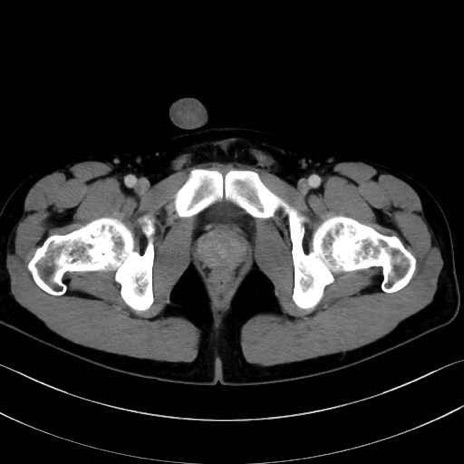

4. 深層外旋六筋(股関節の深部)

梨状筋 (Piriformis)

内閉鎖筋 (Obturator internus)

外閉鎖筋 (Obturator externus)

大腿方形筋 (Quadratus femoris)